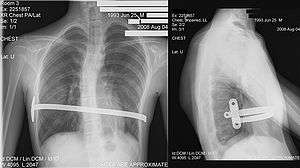

Nuss procedure

Dr. Donald Nuss, based at Children's Hospital of The King's Daughters in Norfolk, Virginia, performed the first minimally invasive repair of pectus excavatum (MIRPE) in 1987[37] and presented it much later at a conference in 1997.[37][38][39] His procedure, widely known as the Nuss procedure, involves slipping in one or more concave steel bars into the chest, underneath the sternum. The bar is flipped to a convex position so as to push outward on the sternum, correcting the deformity. The bar usually stays in the body for about two years, although many surgeons are now moving toward leaving them in for up to five years. When the bones have solidified into place, the bar is removed through outpatient surgery.

Although initially designed to be performed in younger patients (less than 10 years of age) whose sternum and cartilage is more flexible, there are successful series of Nuss treatment in patients well into their teens and twenties. The Nuss procedure is a two-stage procedure (two surgeries, some years apart).